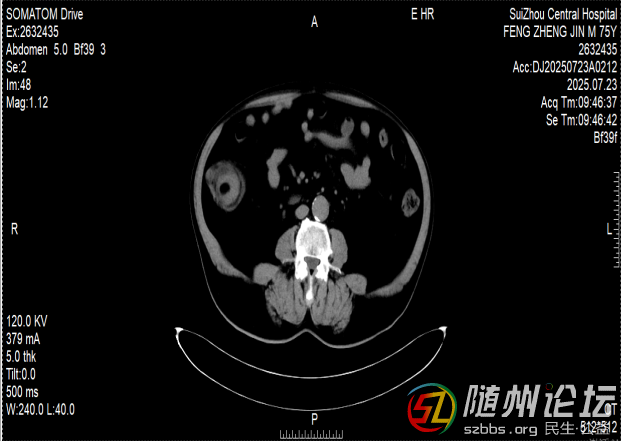

一位76歲的患者,近半年來飽受排便困難的折磨,輾轉(zhuǎn)多家醫(yī)院后,最終在隨州市中心醫(yī)院找到了病因——他的小腸末端,藏著一個(gè)直徑達(dá)6厘米的巨大腫瘤。

這個(gè)腫瘤就像一顆“定時(shí)炸彈”,已多次引發(fā)腸梗阻和腸套疊,導(dǎo)致老人無法正常進(jìn)食,痛苦不堪。由于年事已高,傳統(tǒng)的開腹手術(shù)創(chuàng)傷大、恢復(fù)慢,家屬顧慮重重。

兩難之際,老人在家屬的陪同下找到了隨州市中心醫(yī)院消化內(nèi)鏡中心主任陳志勇。仔細(xì)評(píng)估病情后,陳志勇認(rèn)為,盡管腫瘤巨大、位置特殊,手術(shù)風(fēng)險(xiǎn)很高,但仍有希望通過內(nèi)鏡微創(chuàng)切除,讓患者避免開腹之痛。